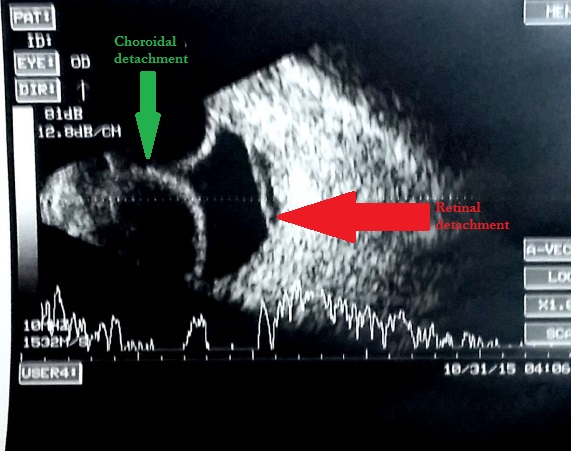

Ultrasonographic features of choroidal detachment (CD)

A CD is denoted by a round mound which is limited by the strong uveoscleral attachments (scleral spur, vortex veins, and optic nerve). It has limited mobility and an A scan passing perpendicularly through a CD shows 'M' (double peak) shape. The shape is typically of a smooth dome, usually not attached to the optic disc. The fluid in the suprachoroidal space may be anechoic (serous CD) or have mild to moderate amplitude point echoes (hemorrhagic CD). When CDs touch each other they are called kissing choroidals, and such cases may be more prone to permanent adhesion and may guide the timing of surgery in suprachoroidal hemorrhage. USG also notes the clot lysis in suprachoroidal hemorrhages and guides timing of surgery, and the location of the suprachoroidal hemorrhage guides the area of drainage.